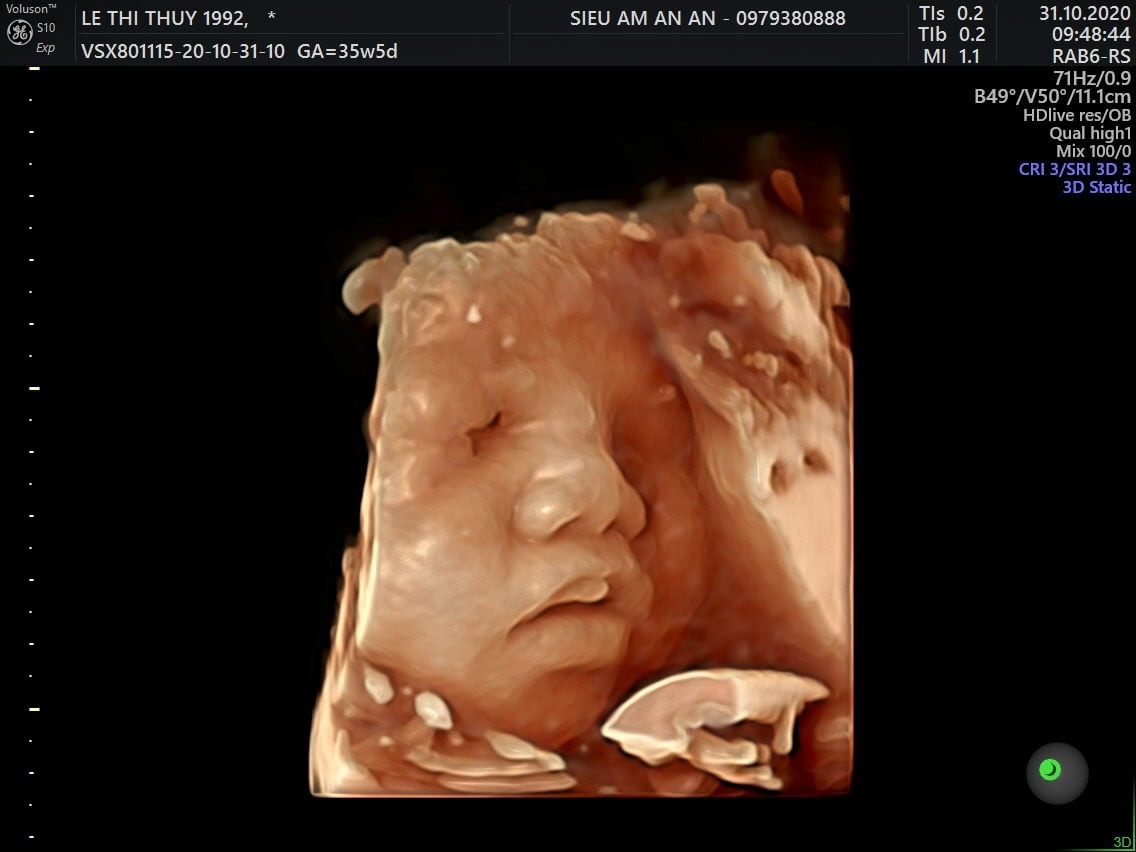

Thai nhi 36 tuần phát triển như thế nào? Ăn gì để con tăng cân, thai 36 tuần gò nhiều, thai 36 tuần nặng bao nhiêu là chuẩn? Qua siêu âm, mẹ có thể thấy hình ảnh một bé yêu mũm mĩm đáng yêu rất giống với em bé sơ sinh hoàn chỉnh. Điều này khiến nhiều mẹ thấy trái tim mình như tan chảy, bé yêu dường như đang đến rất gần rồi.

Chỉ còn khoảng 4 tuần nữa em bé sẽ chào đời, mẹ chắc chắn đang rất tò mò về sự phát triển của bé ở giai đoạn này. Khi mang thai tuần 36, mẹ dễ dàng theo dõi được hình thái của bé qua siêu âm. Các bộ phận chân, tay cử động nhẹ nhàng vô cùng đáng yêu. Hình ảnh mũm mĩm, mập mạp của bé thật sự khiến trái tim mẹ nào cũng phải tan chảy.

Ngược lại, nếu cơn gò nhiều đi kèm các triệu chứng ra máu, vỡ ối, rò rỉ ối, chóng mặt, ngất xỉu, đau liên tục, mẹ cần đến bệnh viện kiểm tra sức khỏe càng sớm càng tốt. Rất có thể mẹ đang đối mặt với hiện tượng sinh non. Qua hình ảnh thai nhi 36 tuần từ máy siêu âm, bác sĩ sẽ đưa ra chỉ định tối ưu nhất.